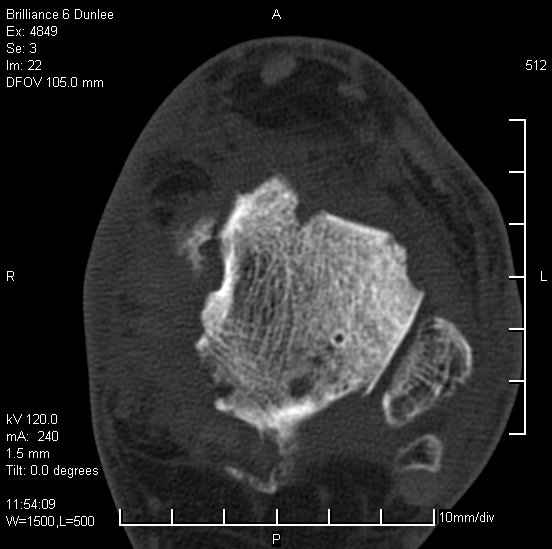

Асептический некроз таранной кости.

На лечении находится пациент 35 лет. Травма в сентябре 2008 г.- открытый вывих таранной кости

В день травмы ПХО, вправление вывиха, трансартикулярная фиксация. Рана зажила первично. С января нагрузка на конечность. С конца апреля- болевой синдром. На рентгенограммах и КТ признаки ас. некроза таранной кости, артроз подтаранного и голеностопного суставов.